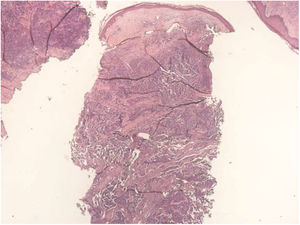

A 67-year-old male patient presented to the Dermatology Outpatient Clinic with a history of systemic arterial hypertension, type 2 diabetes mellitus, and dyslipidemia, using insulin, losartan, hydrochlorothiazide, atenolol, acetylsalicylic acid, rosuvastatin, and fibrate, six months after an asymptomatic, rapidly growing, erythematous-violaceous nodule (Fig. 1) measuring 3cm had appeared on his right leg, without palpable lymphadenomegalies. Incisional biopsy of the lesion (Figs. 2 and 3) revealed, in the histopathology, a dermal tumor with trabecular arrangement, composed of small blue cells with scarce cytoplasm and compact nuclei. Immunohistochemistry was positive for chromogranin and cytokeratin 20, signaling the diagnosis of MCC. In the outpatient return, we requested a computed tomography (CT) scan of the chest, abdomen, and pelvis, which did not show involvement of the internal organs or lymph node enlargement. In addition to the immunosuppression tests, the serologies were also all negative. The patient was then referred for oncological surgery, where sentinel lymph node screening was performed, which did not show any neoplastic involvement. Extensive excision, measuring 7.7cm×6.8cm×0.8cm, was performed and the histopathology demonstrated MCC with resection margins free of involvement.